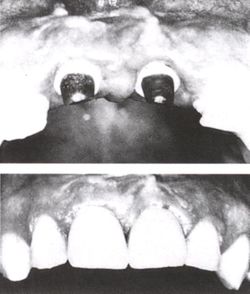

While studying bone cells in a rabbit femur using a titanium chamber, Branemark was unable to remove it from bone. His realization that bone would adhere to titanium led to the concept of osseointegration and the development of modern dental implants. The original xray of the chamber embedded in the rabbit femur is shown (made available by Branemark).

In the 1950s research was being conducted at Cambridge University in England to study blood flow in vivo. These workers devised a method of constructing a chamber of titanium which was then embedded into the soft tissue of the ears of rabbits. In 1952 the Swedish orthopaedic surgeon, Per-Ingvar Brånemark, was interested in studying bone healing and regeneration. During his research time at Lund University he adopted the Cambridge designed "rabbit ear chamber" for use in the rabbit femur. Following the study, he attempted to retrieve these expensive chambers from the rabbits and found that he was unable to remove them. Brånemark observed that bone had grown into such close proximity with the titanium that it effectively adhered to the metal. Brånemark carried out further studies into this phenomenon, using both animal and human subjects, which all confirmed this unique property of titanium.

Although Brånemark had originally considered that the first work should centre on knee and hip surgery, he finally decided that the mouth was more accessible for continued clinical observations and the high rate of edentulism in the general population offered more subjects for widespread study. He termed the clinically observed adherence of bone with titanium as "osseointegration". In 1965 Brånemark, who was by then the Professor of Anatomy at Gothenburg University in Sweden, placed his first titanium dental implant into a human volunteer.[5](p. 626)